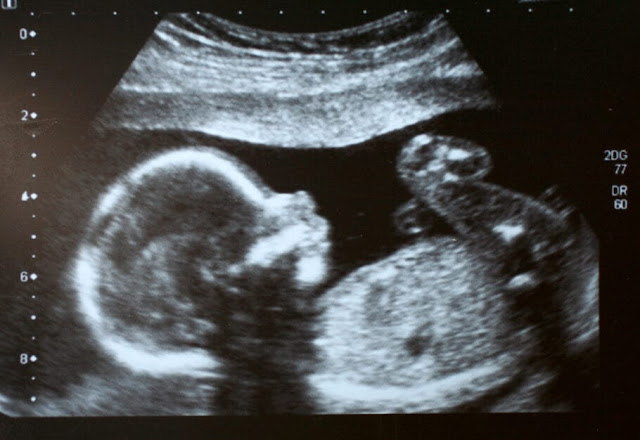

Uma gestante de Israel infectada com a covid-19 perdeu o filho que também carregava o vírus, na 36ª semana de gestação. O caso foi relatado pelo hospital israelense, que informou não ser possível ainda não afirmar que a causa da morte do feto tenha sido o novo coronavírus.

Segundo a imprensa local, a mãe procurou atendimento médico quando começou a passar mal. Os médicos descobriram que o feto havia morrido no útero e um teste de laboratório realizado posteriormente revelou que o bebê também estava infectado com o vírus.

Um caso idêntico foi reportado na semana passada em Israel, quando uma mulher de 29 anos perdeu seu filho na 25ª semana de gravidez na cidade de Ashdod.